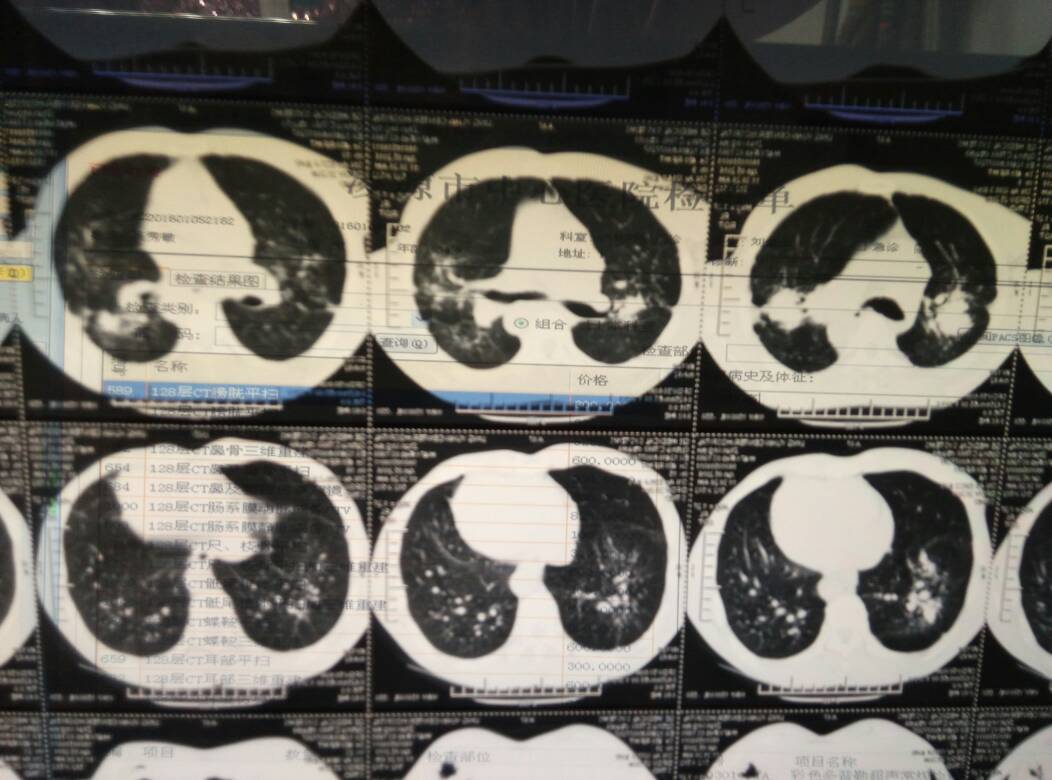

矽肺 ( silicosis )